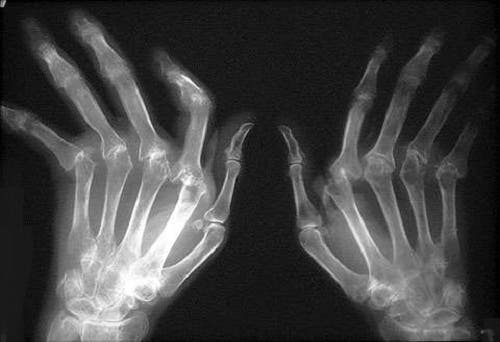

Artritis

La artritis la causa la alteración o desgaste del cartílago, que es el tejido que se encuentra en las articulaciones. Se encarga de hacer que los movimientos sean mucho más suaves y no provoquen roces entre los huesos.

Hasta el momento se desconoce la causa de la artritis y además no existe ningún medicamento que la elimine.Hay fármacos más eficaces que otros pero de base se suelen recetar medicamentos anti-inflamatorios y antiálgicos. Por tanto la relación de la artritis con el consumo escaso de agua no está demostrada como tal.

No obstante, es importante informar a todas las personas que sufren de esta enfermedad, que la causa de su dolencia se puede deber a la falta de hidratación.

Los cartílagos contienen gran cantidad de agua para poder mantener las articulaciones bien lubricadas.Así los huesos no rozan entre sí y los los movimientos son más suaves. Si esto se pierde se forman lesiones típicas de la artritis.